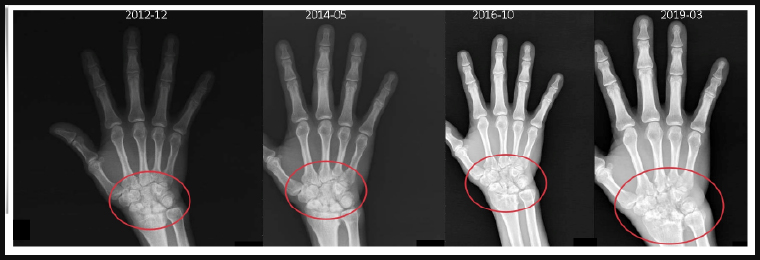

以張先生的案例為例,雖然他的發炎指數維持正常,但其手部關節內部已悄悄出現破壞,這種「骨侵蝕」是不可逆的變化,若置之不理,最後可能會導致關節變形,影響手部功能,無法正常握持工具,對日常生活及工作造成重大影響。經由比對張先生近年來的X光檢查影像,發現確實已有明顯異常,於是改用另1款新型生物製劑,在治療1段時間後,關節破壞進程趨緩,病情受穩定控制,張先生也已順利恢復原本的生活步調。

▲經比對張先生近年來的X光影像,可看出關節破壞程度越發嚴重,於是改用另1款新型生物製劑以控制病情。(圖/亞洲大學附屬醫院提供)